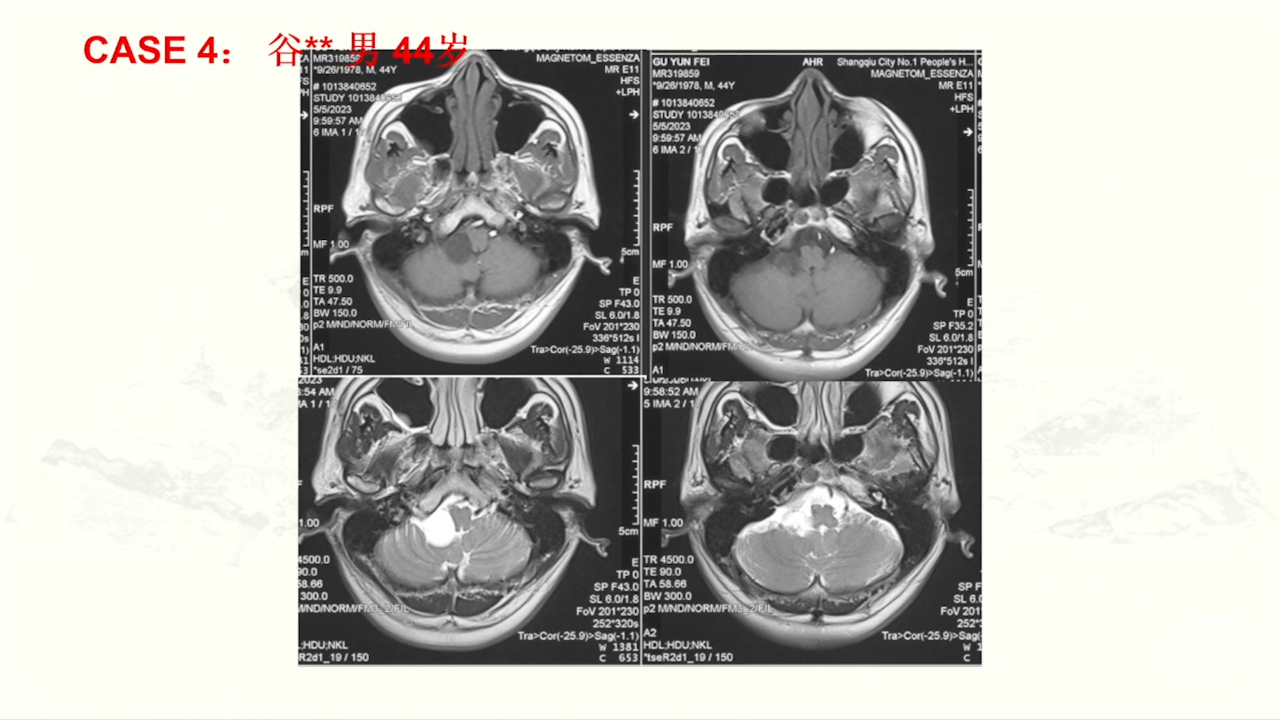

颈静脉孔区肿瘤充分显露是硬道理。肿瘤越大,工作通道越宽。颈静脉孔扩大越明显,开放颈静脉孔越容易。

卜博教授:颈静脉孔区肿瘤:解剖及156例经验